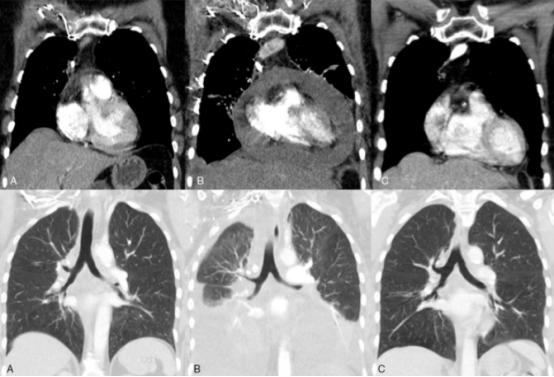

A:免疫治疗前;B:免疫治疗发生超进展;C:挽救化疗后

2周后,患者因呼吸急促入院,影像学检查发现大量心包积液和胸腔积液。为什么PD-L1高表达的她在接受了免疫治疗后会出现了如此令人咋舌的疾病恶化?医务人员再一次检测了PD-L1的表达量,结果为……0%!

这位患者被评估为“超进展”,不得不停止了免疫治疗。紧接着,作为挽救方案,患者接受了卡铂 培美曲塞的化疗,3个周期后,患者停止治疗。虽然在化疗过程中出现了严重的憩室炎,但在抗生素配合治疗后,多次定期复查发现肿瘤消失,并维持无病状态长达20个月。